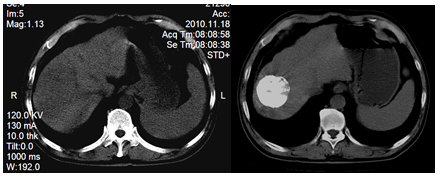

(一)、患者、男、56岁,肝硬化多次消化道出血,合并多发肝肿瘤,综合医院建议放弃其他治疗,行中医治疗。在我院介入科采用中药制剂与进口碘化油栓塞后结合中医治疗,3年后复查肿瘤基本稳定。